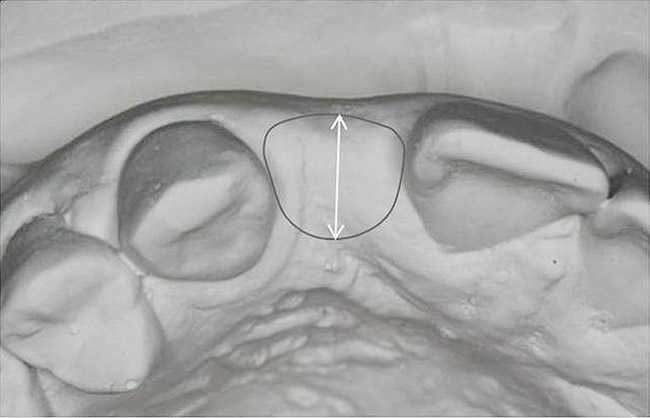

Figure 14 Exploiting study casts for planning single-tooth implant placement and restoration: Mounted study casts permit an estimation of available bone volume (Fig 13); measure the bound edentulous space inter-tooth dimensions (Fig 14); measure the avail

Figure 14